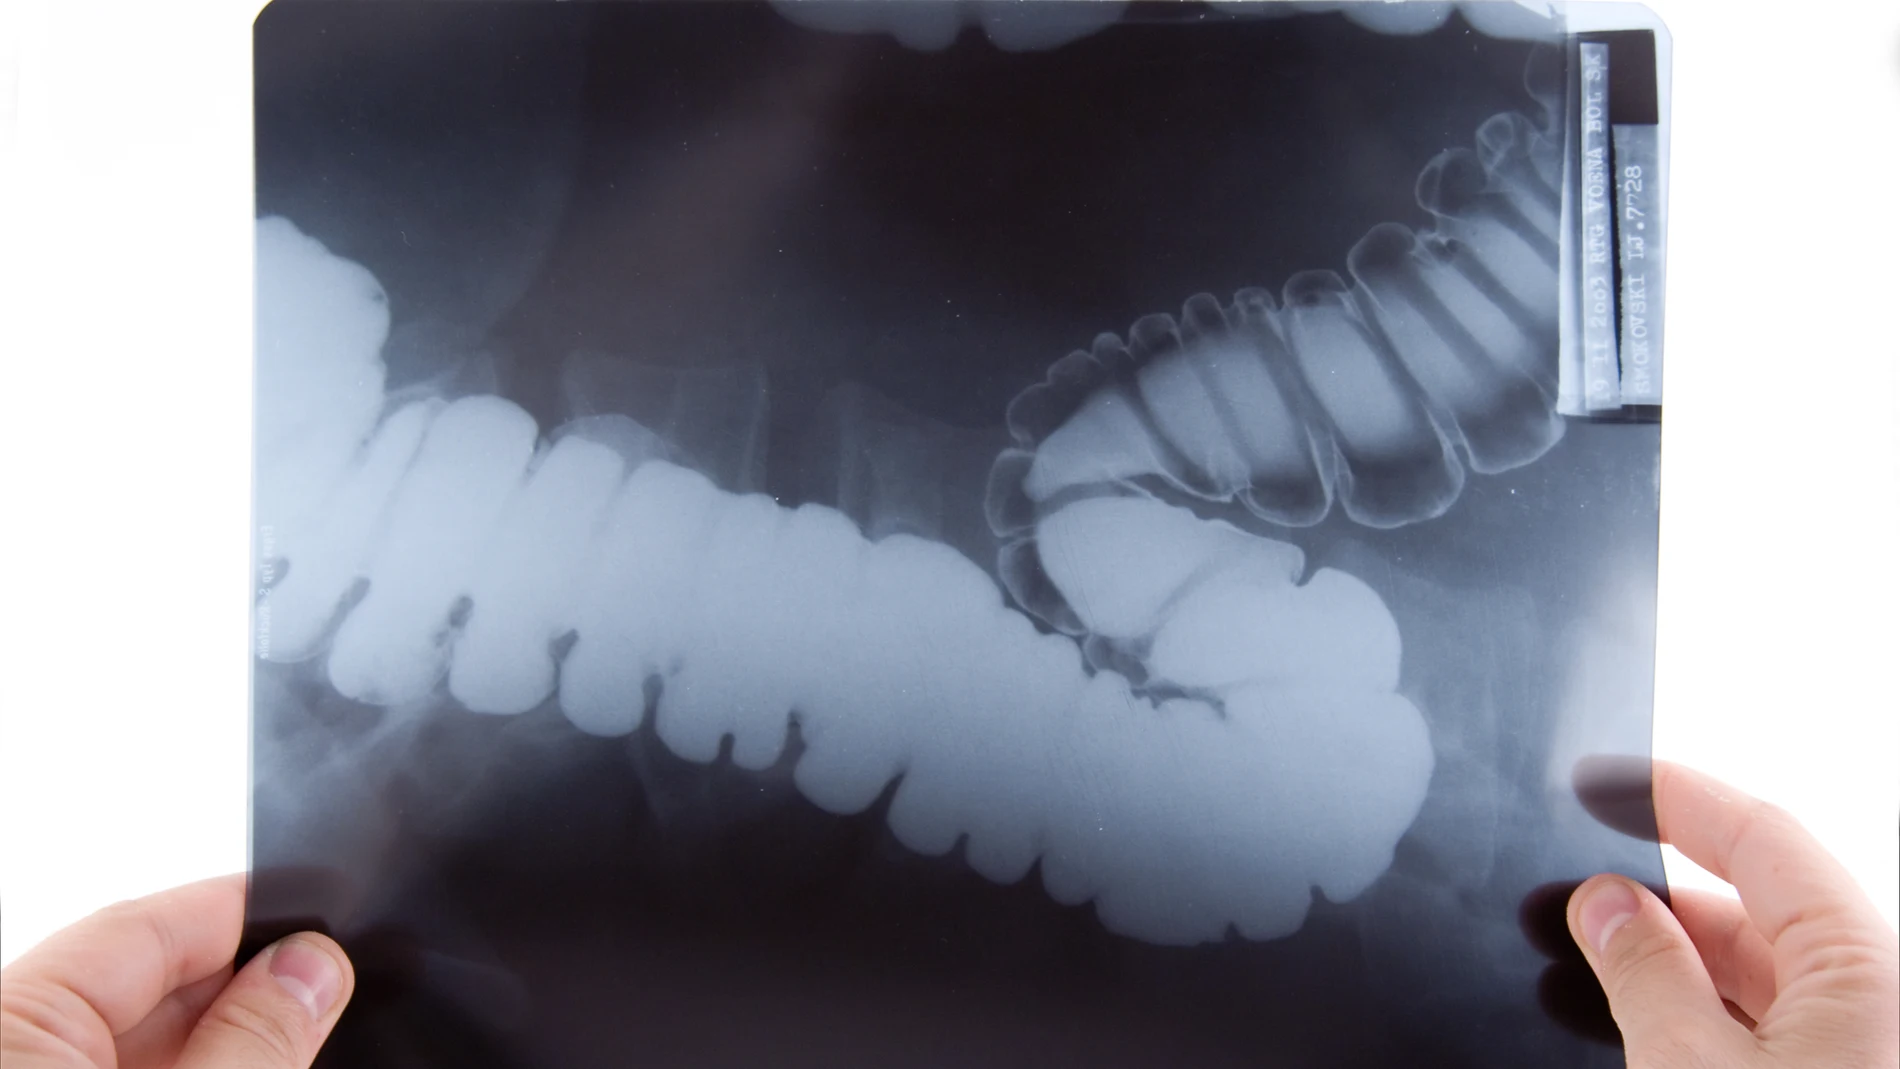

El cáncer de recto es un tipo de tumor que se desarrolla en los últimos centímetros del intestino grueso, justo antes del ano. Es uno de los más comunes en Europa, con más de 125.000 personas diagnosticadas cada año. El tratamiento consiste en la extirpación quirúrgica del tumor, una operación mayor que puede afectar la función sexual, la continencia y la calidad de vida. Si bien la radio y la quimioterapia ya se usan para reducir su tamaño antes de la cirugía, cada vez están más en auge estrategias que la evitan en pacientes cuyo tumor ha desaparecido tras el tratamiento y buscan preservar el recto.

En cambio, el cáncer anal afecta los primeros centímetros del intestino. Aunque es poco frecuente (se diagnostica anualmente en unas 14.000 personas en Europa), es más sensible a la radioterapia, y ensayos clínicos previos han demostrado que una combinación de radio y quimio puede evitar la necesidad de una cirugía mayor y una colostomía permanente. Sin embargo, el enfoque estándar actual conlleva altas tasas de efectos secundarios a corto y largo plazo.